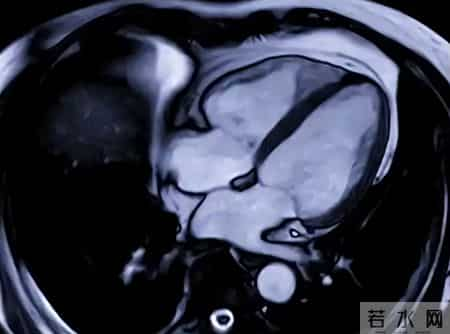

如果上述自我调理后仍不见好转,建议带上既往检查资料,专科医生可进一步判断是否需要心脏磁共振、动态心电监测等更精细的检查,为健康把关。